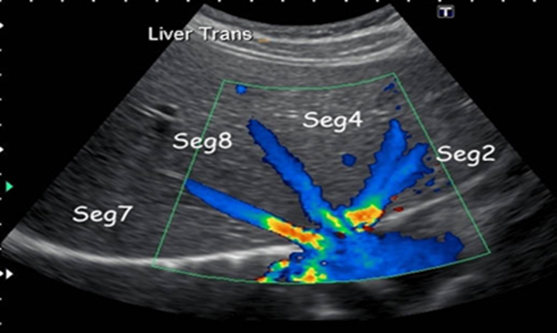

Siêu âm bụng tổng quát: giúp quan sát các cơ quan trong ổ bụng như gan, mật, tụy, lách, thận, bàng quang, tử cung (phần phụ), tuyến tiền liệt… thông qua những hình ảnh thu được

Hình 4. Kết quả siêu âm.

Siêu âm là một kĩ thuật mang lại rất nhiều lợi ích trong việc chẩn đoán lẫn tầm soát vì thời gian khảo sát ngắn, không gây đau, không có tác dụng phụ. Qua siêu âm có thể phát hiện được những bất thường các cơ quan bên trong cơ thể như:

Gan: viêm, xơ gan, gan nhiễm mỡ, áp xe gan, u gan lành hay ác tính.

Mật: sỏi mật, u, viêm túi mật, polyp túi mật, dị dạng đường mật.

Tụy: u tụy, viêm tụy cấp và mạn, tụy bẩm sinh

Lách: lympho lách, áp xe lách, lách to, các u lách.

Hệ tiết niệu: sỏi, viêm, ung thư thận, viêm bàng quang, u bàng quang

Hệ sinh dục: u nang buồng trứng, ung thư buồng trứng, u xơ tử cung, viêm tiền liệt tuyến, ung thư tuyến tiền liệt.

Hệ tiêu hóa: viêm ruột thừa, viêm ruột, u, xoắn ruột, lồng ruột.

Khác: Dịch ổ bụng, dịch màng phổi, dịch màng tim, …